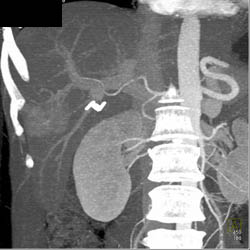

Focal Nodular Hyperplasia (FNH)